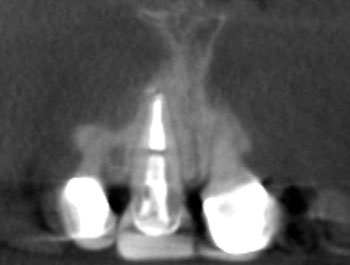

Fig. 4: Recall CBCT.

The patient returned in three months, when resolution of symptoms, healing of the deep probing defect and bone regeneration were confirmed. The tooth was obturated, and a foundational restoration was placed before the rubber dam was removed. Fourteen years of follow-up confirmed long-term periradicular health. The amount of appreciation and gratitude that this patient expressed reminds us that each individual tooth demands our best efforts.